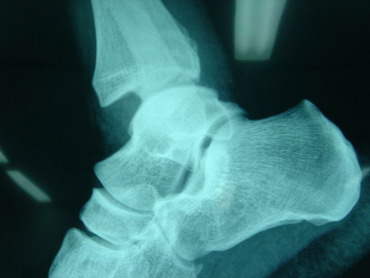

14 - 5 - 07 El torero se interviene hoy a la 12,30 horas en la Clínica Sagrado Corazón de Sevilla. Se confirma diagnóstico provisional hecho en la enfermería de la plaza de Osuna. Fractura de tibia y peroné. Con las siguientes connotaciones: La fractura de peroné es completa y compleja consta de 4 fragmentos diferentes con desplazamiento de los mismos. es decir una fractura conminuta. La tibia presenta fractura maleolar con desplazamiento y además con respecto al tobillo existe una subluxación de la articulación debida a la rotura o explosión de la cápsula articular con desflecamiento de la misma. En resumen un cuadro complejo de tobillo inestable que precisa intervención quirúrgica inmediata. Se estabilizan las fracturas, se sutura la cápsula anterior, se reduce la subuxación, se administran factores de crecimiento y se inmoviliza extremidad. Pronóstico grave. Se estima un tiempo de recuperación de 90 días. Dr. Minguet. Dr. Periañez. Dr. Vaz. Dr. Morales |